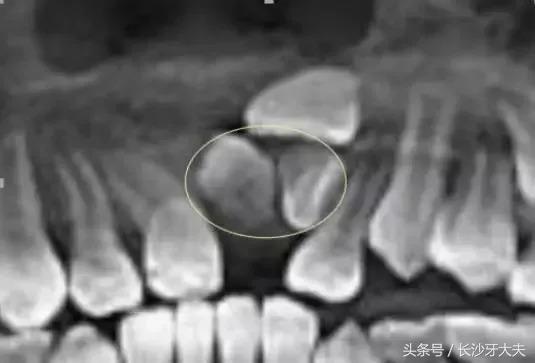

我不喜欢被约束,当普通牙齿都像小士兵一般整齐排队时,我却跑去探索骨内空间了。

也有少数情况下可能导致含牙囊肿的发生,若无视它继续生长,骨质逐渐向周围膨胀,则会形成面部畸形,根据不同部位可出现相应的局部症状。